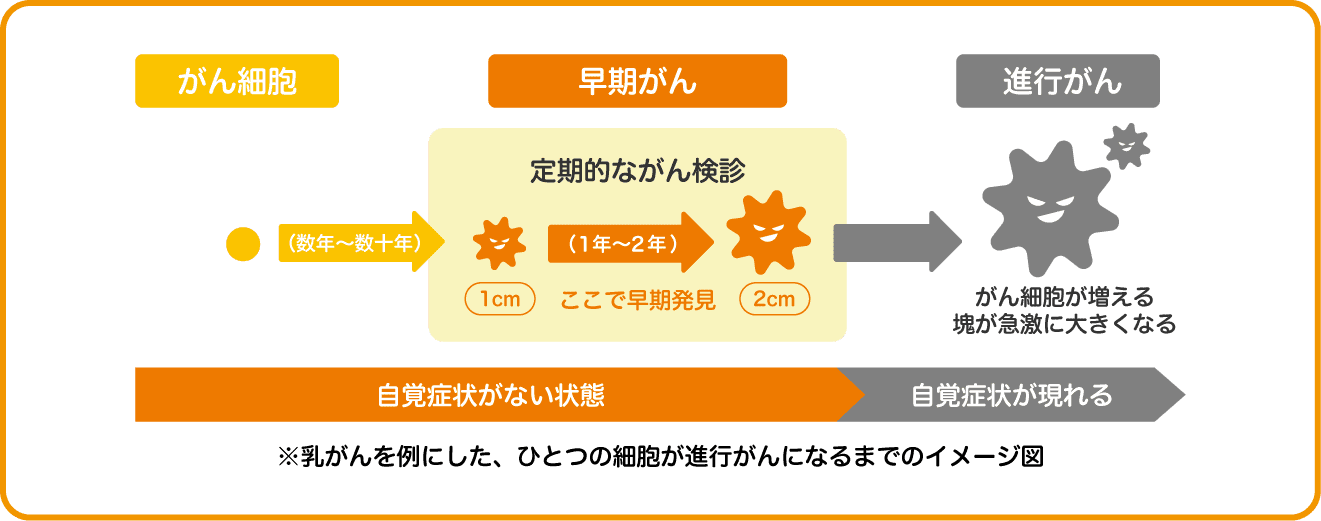

私たちの体は、約60兆個の細胞からできています。細胞の⼀部は毎⽇更新されていますが、正常な細胞の遺伝⼦に傷がついた異常な細胞が発⽣することがあります。 これをがん細胞といいます。

がん細胞は健康な体にも発⽣しますが、通常は体に備わった免疫が働いてがん細胞 を死滅させます。この免疫の効果が得られずにがん細胞が無限に増えて、かたまりになったものをがんといいます。⽇本⼈の2⼈に1⼈はがんになり、3⼈に1⼈はがんが原因で亡くなっています。がんは⽇本⼈の死亡原因の1位です。

がんを早期に発⾒し、早期のうちに適切な治療を⾏うことでがんによる死亡を減らすことが出来ます。早期発⾒の最⼤のメリットは⾃覚症状のない早期の状態でがんを⾒つけられること。⾝体の負担、⼊院⽇数、医療負担も少なくて済みます。